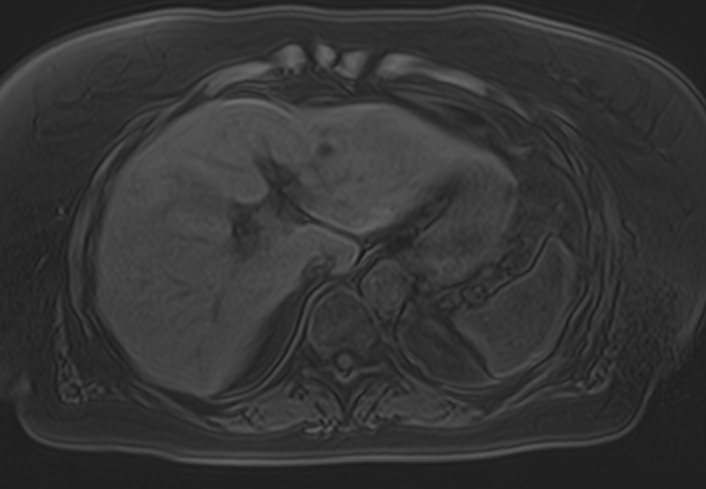

Магнитно-резонансная томография является современным наиболее информативным неинвазивным методом диагностики заболеваний печени. С помощью использования магнитного поля, обладающего высокой индукционной мощностью, МРТ позволяет получать послойные изображения органа и окружающих тканей и выявлять патологические изменения в печени на самых ранних стадиях развития, когда другие методы диагностики не дают результатов. Кроме того, процедура безболезненна и безопасна, так как организм не подвергается воздействию вредного рентгеновского излучения. Это позволяет назначать МРТ неоднократно в течение короткого промежутка времени, например, для оценки динамики состояния органа на фоне лечения.

В клинике «Доступная медицина» исследование проводится на современном высокопольном томографе экспертного класса TOSHIBA VANTAGE TITAN 1,5 Тесла. Аппарат послойно сканирует исследуемую зону в трех плоскостях с шагом от 1 мм, при этом получая данные о структуре органа в мельчайших подробностях. Инновационные компьютерные программы реконструируют данные в трехмерные модели органа, отображающие состояние не только паренхимы печени, но и внутрипеченочных желчных протоков и сосудистой системы.

Использование в процедуре МР-сканирования контрастирующих красителей позволяет выявить и охарактеризовать поражения печени размером от 1 мм, отличать доброкачественные и злокачественные новообразования, метастазы.

На томографических снимках хорошо заметны:

- доброкачественные очаговые поражения печени (гемангиома, очаговая узловая гиперплазия, гепатоцеллюлярная аденома, кисты (в том числе и паразитарные), липома, абсцесс, инфекции);

- злокачественные очаговые поражения печени;

- заболевания желчных протоков и желчного пузыря;

- диффузные болезни печени (стеатоз, воспалительные заболевания (вирусный гепатит, склерозирующий холангит), цирроз;

- патологии сосудов (тромбозы, артерио-венозные мальформации)

- рубцовые изменения после травм или операций